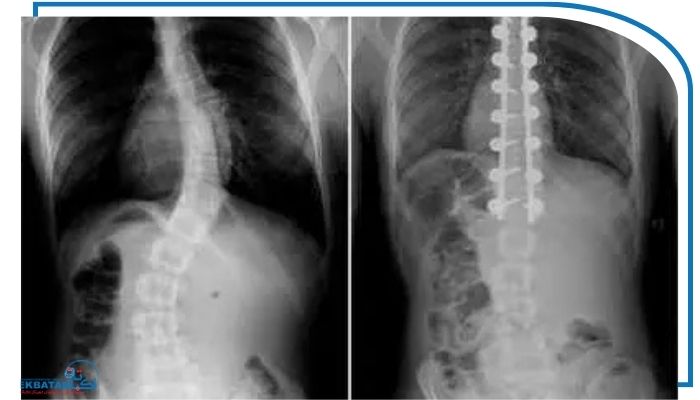

رادیولوژی ساده برای مشاهده شکل مهره‌ها، میزان قوس، وجود شکستگی‌های فشاری و تهیه عکس انحراف ستون فقرات مورد استفاده قرار می‌گیرد.

جراحی

جراحی آخرین گزینه و برای مواردی است که کجی شدید شده درد مقاوم به درمان وجود دارد یا فشار روی نخاع و ریشه‌های عصبی ایجاد شده است. نوع جراحی بر اساس سن وضعیت عمومی بیمار و میزان درگیری مهره‌ها انتخاب می‌شود.